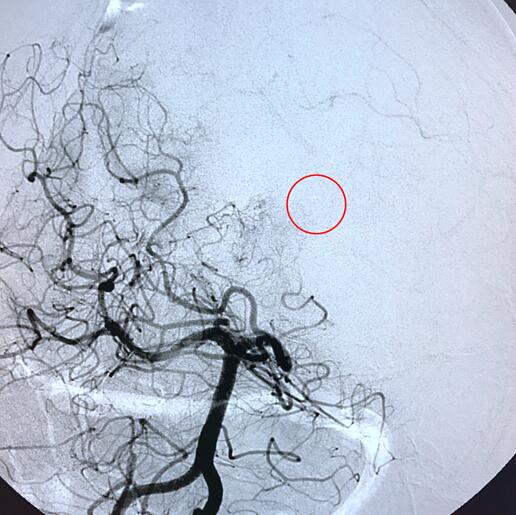

患者女性,以“脑动静脉畸形伽马刀术后11年,再次脑室出血1月余”入院。11年前因脑室出血检查发现动静脉畸形,行伽马刀治疗,恢复至日常生活自理,1月余前再次出现脑室出血,行CTA及DSA检查示脑动静脉畸形合并动脉瘤,先后至多家医院就诊考虑治疗难度大。

我们经仔细分析及多科室讨论认为动静脉畸形较小,手术切除创伤大,合并动脉瘤再行放射治疗的效果不佳,介入栓塞,但由于供血动脉细小,处于末梢,难度大。术中克服困难,成功将微导管插入畸形团,注胶栓塞,一次治愈,术后患者无不适,查体正常。以下为术前、术中及术后相关影像。

图2 DSA正位显示动静脉畸形及动脉瘤

图3 DSA侧位显示动静脉畸形及动脉瘤

图4 DSA工作角度显示动静脉畸形及动脉瘤

图5 微导管到位后造影显示动静脉畸形及动脉瘤

图6 栓塞后造影显示动静脉畸形及动脉瘤消失